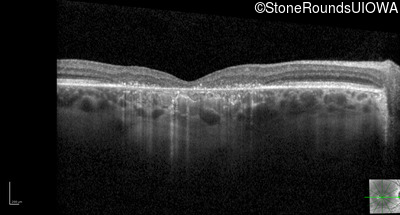

Optical Coherence Tomography - Right - 20/160

Exemplar / OCT Stack